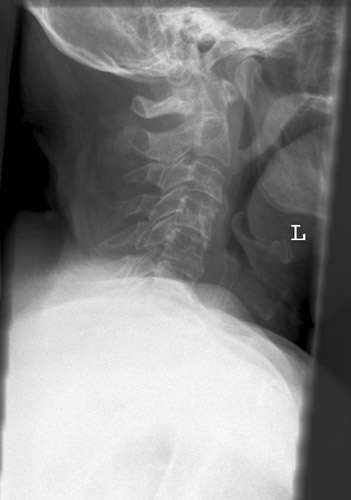

HWS seitlich

85_2.jpg

Fehler

Der unterste Halswirbel wird durch die Schultermuskulatur verdeckt.

Abhilfe

Arme des Patienten stark nach unten ziehen, am besten mit Gewichten beschweren (evtl. Spezialaufnahme in der Stellung des "Wasserskifahrers" "Übergang") .